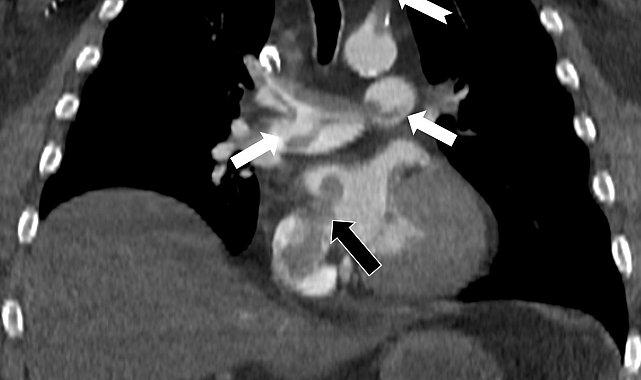

Bir dönem Özel Denizli Tekden Hastanesi'nde de görev yapan Prof. Dr. Nevzat Karabulut'un yaptığı çalışmada; akciğerin bilgisayarlı tomografi anjiyografisi sayesinde toplar damarlardan kaynaklanan pıhtının akciğer damarlarını tıkaması yanında, kalpteki delik nedeniyle kalbin sağ tarafından sol tarafına geçerek ana atardamara ulaştığı ve sol kol damarını tıkadığı gösterildi.

Emboli görüntülemesi konusunda çok sayıda bilimsel çalışması bulunan Prof. Dr. Karabulut, genelde bacak damarlarından kaynaklanan pıhtıların ölümcül olabilen akciğer embolisine yol açması yanında, kalp deliği olan hastalarda ana atardamar yoluyla beyin, kol ve bacak gibi vücudun diğer bölgelerine de geçerek ani damar tıkanmasına (paradoks emboli) bağlı bulgulara yol açtığını belirtti. Prof. Dr. Karabulut'un çalışmasında nedeni bilinmeyen pıhtı atmalarında kalpteki gizli deliklerin mutlaka araştırılması gerektiği vurgulanarak ekokardiyografi ve bilgisayarlı tomografi tetkiklerinin erken ve doğru tanı koymada hayat kurtarıcı rolüne dikkat çekildi.